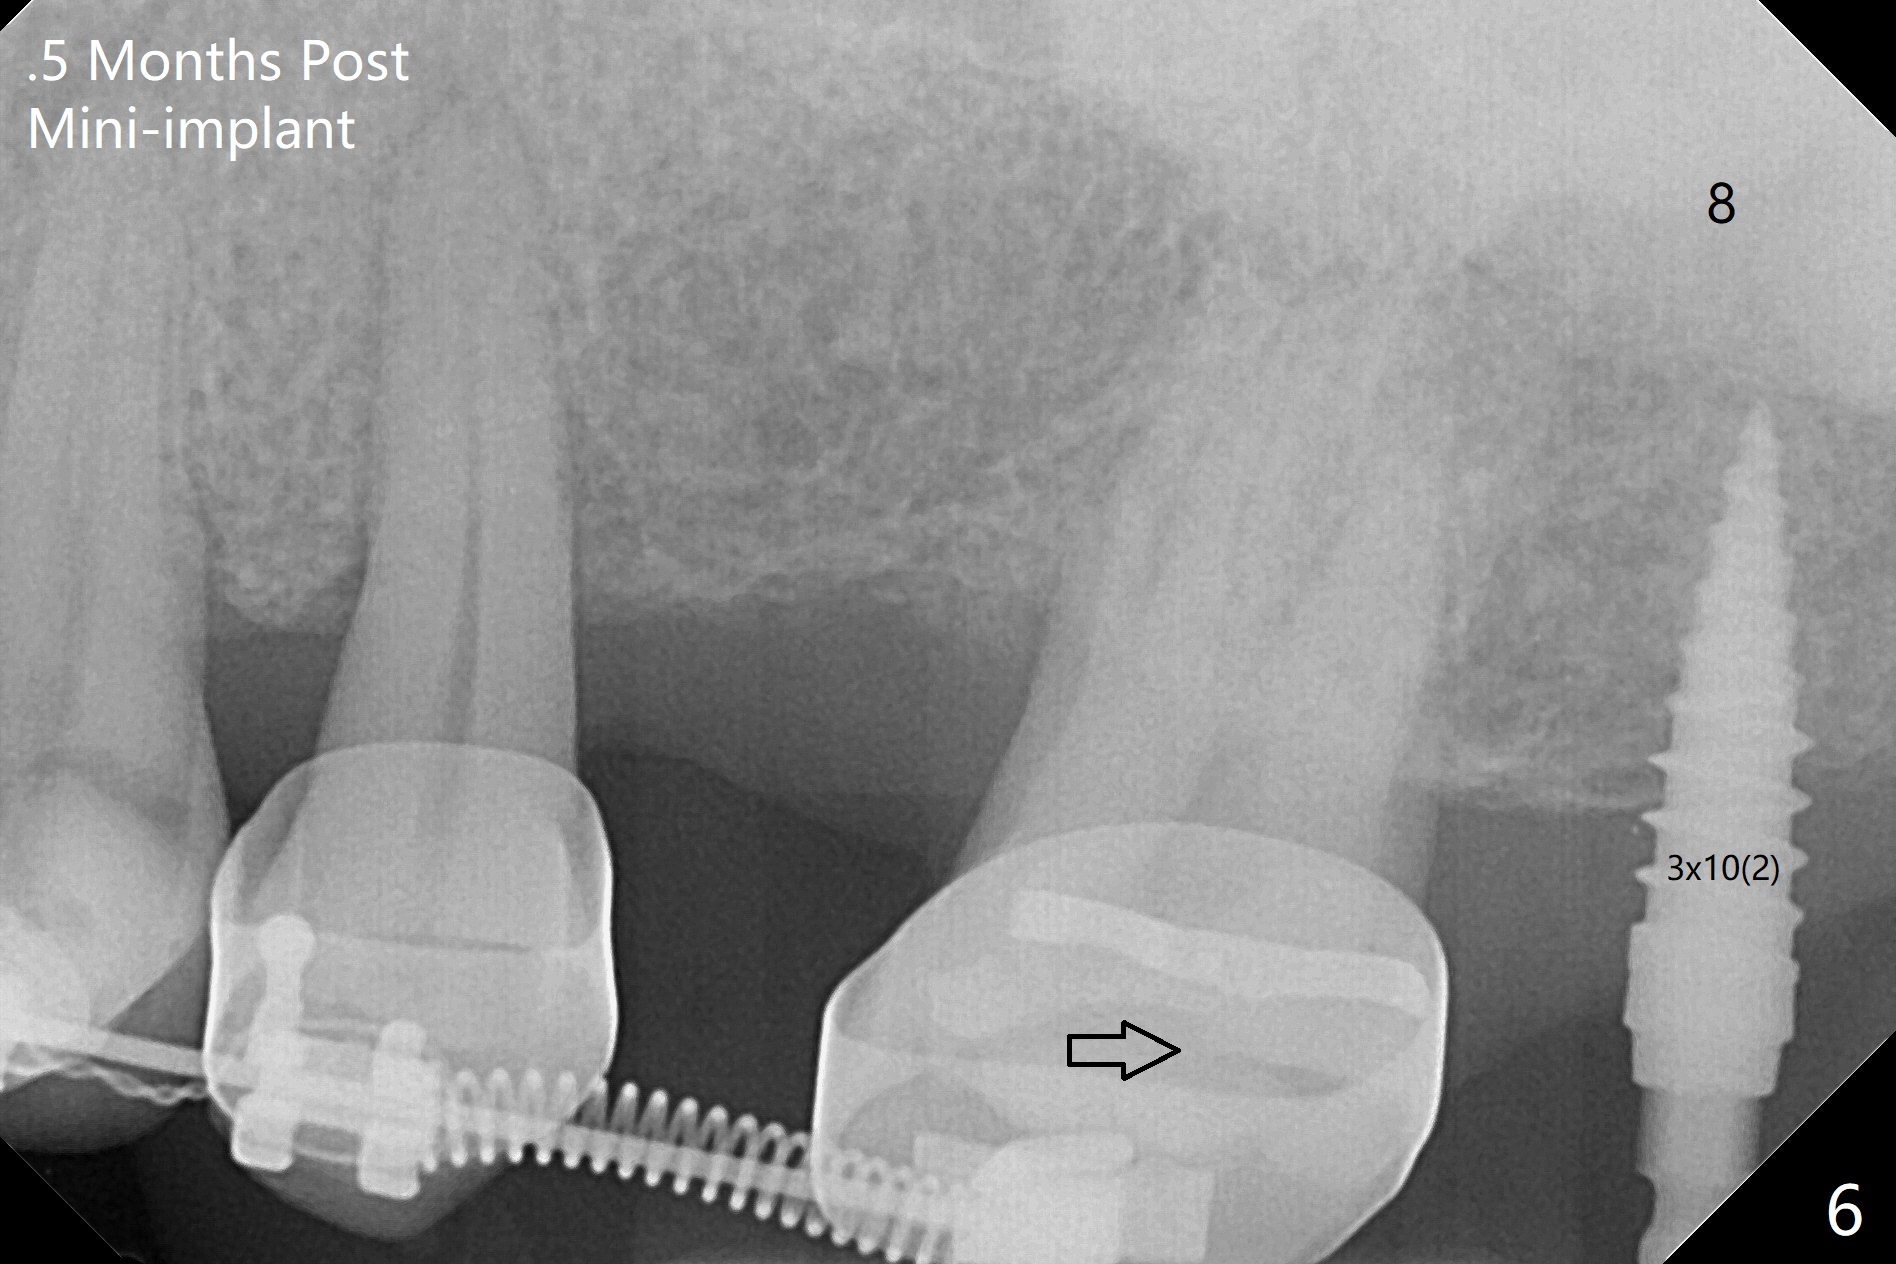

为了在左上6,左下7种植,使用右上3至左上5作为支抗推左上7远中,但是六个月效果不显著(图一),CT显示阻生牙(图一,二:8)没有阻挡。7远中植入1.6x8毫米微型植体,不过接近7根尖(图三),微型植体应该改变角度,而且往远中颊侧移位。最后效果不错(图四),植体马上启用(图五),而且同时取模做左下7导板。在微型植体牵引下,左上7的确往远中移位(图六,与图四对比),但是植体松动,马上植入3x10(2)毫米一段式植体,由于8阻挡,后者没有完全就位,稳定性差,没有启动。几天后也脱落。病人急着完成治疗,因为咀嚼困难。补救方法便是拔除阻生牙9(图七:x),让植体完全就位。切开后发现牙槽嵴处严重骨质吸收缺损(图八:D),离7很近,不适合种植。拔除8后(图九:S(socket)),两处植骨(粘性,图十),覆盖PRF膜,缝合。矫正九个月6空间相当双尖牙(图十二),还想增加2毫米才种植,病人急于完成治疗,所以再次植入微型植体,不同之处是切开,发现7远中颊侧骨质密度低(用探针),因此微型植体在腭侧植入(图十一:P),扭力似乎高,1.6x8毫米植体仿佛植入8牙槽窝(图十二:红虚线)。微型植体牵引一个月,磨牙缺牙间隙大约前磨牙大小,准备在远中(图十三)植入直径小植体(图十四),当后者整合时,用它继续推7。